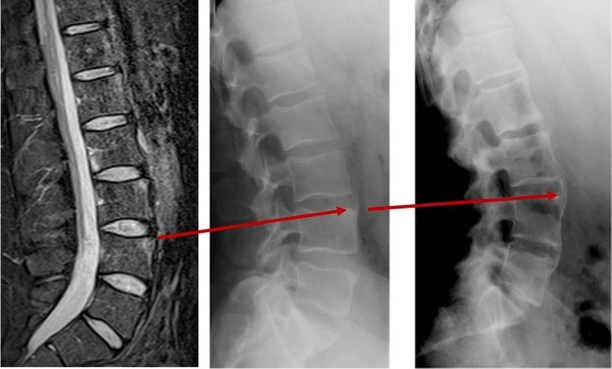

Skanningsbilleder

Smerterne i ryggen kan være udtryk for andre tilstande i ryggen, og derfor benytter lægen hyppigt billedundersøgelser i udredningen. En særlig MR-skanning af bækkenled og hele rygsøjlen vil kunne vise gigtforandringer tidligt i forløbet. Almindelige røntgenbilleder af bækkenled og rygsøjle viser ofte først forandringerne efter mange års sygdom.

MR-skanning og røntgenbilleder af rygsøjlen set fra siden. Der ses sammenvoksning af ryghvirvler henover bruskskiven (diskus).

Normal røntgen af bækkenled

Sammenvoksede bækkenled efter mange års sygdom